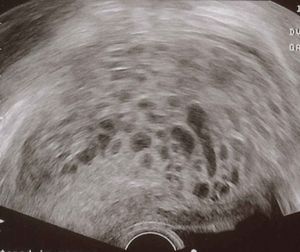

초음파 사진에서 기태는 포도송이("포도송이 떼", "벌집 자궁", "눈보라")와 유사하게 나타난다.[14] CT 촬영을 통해 자궁강 내에 과립상의 구조가 관찰된다.